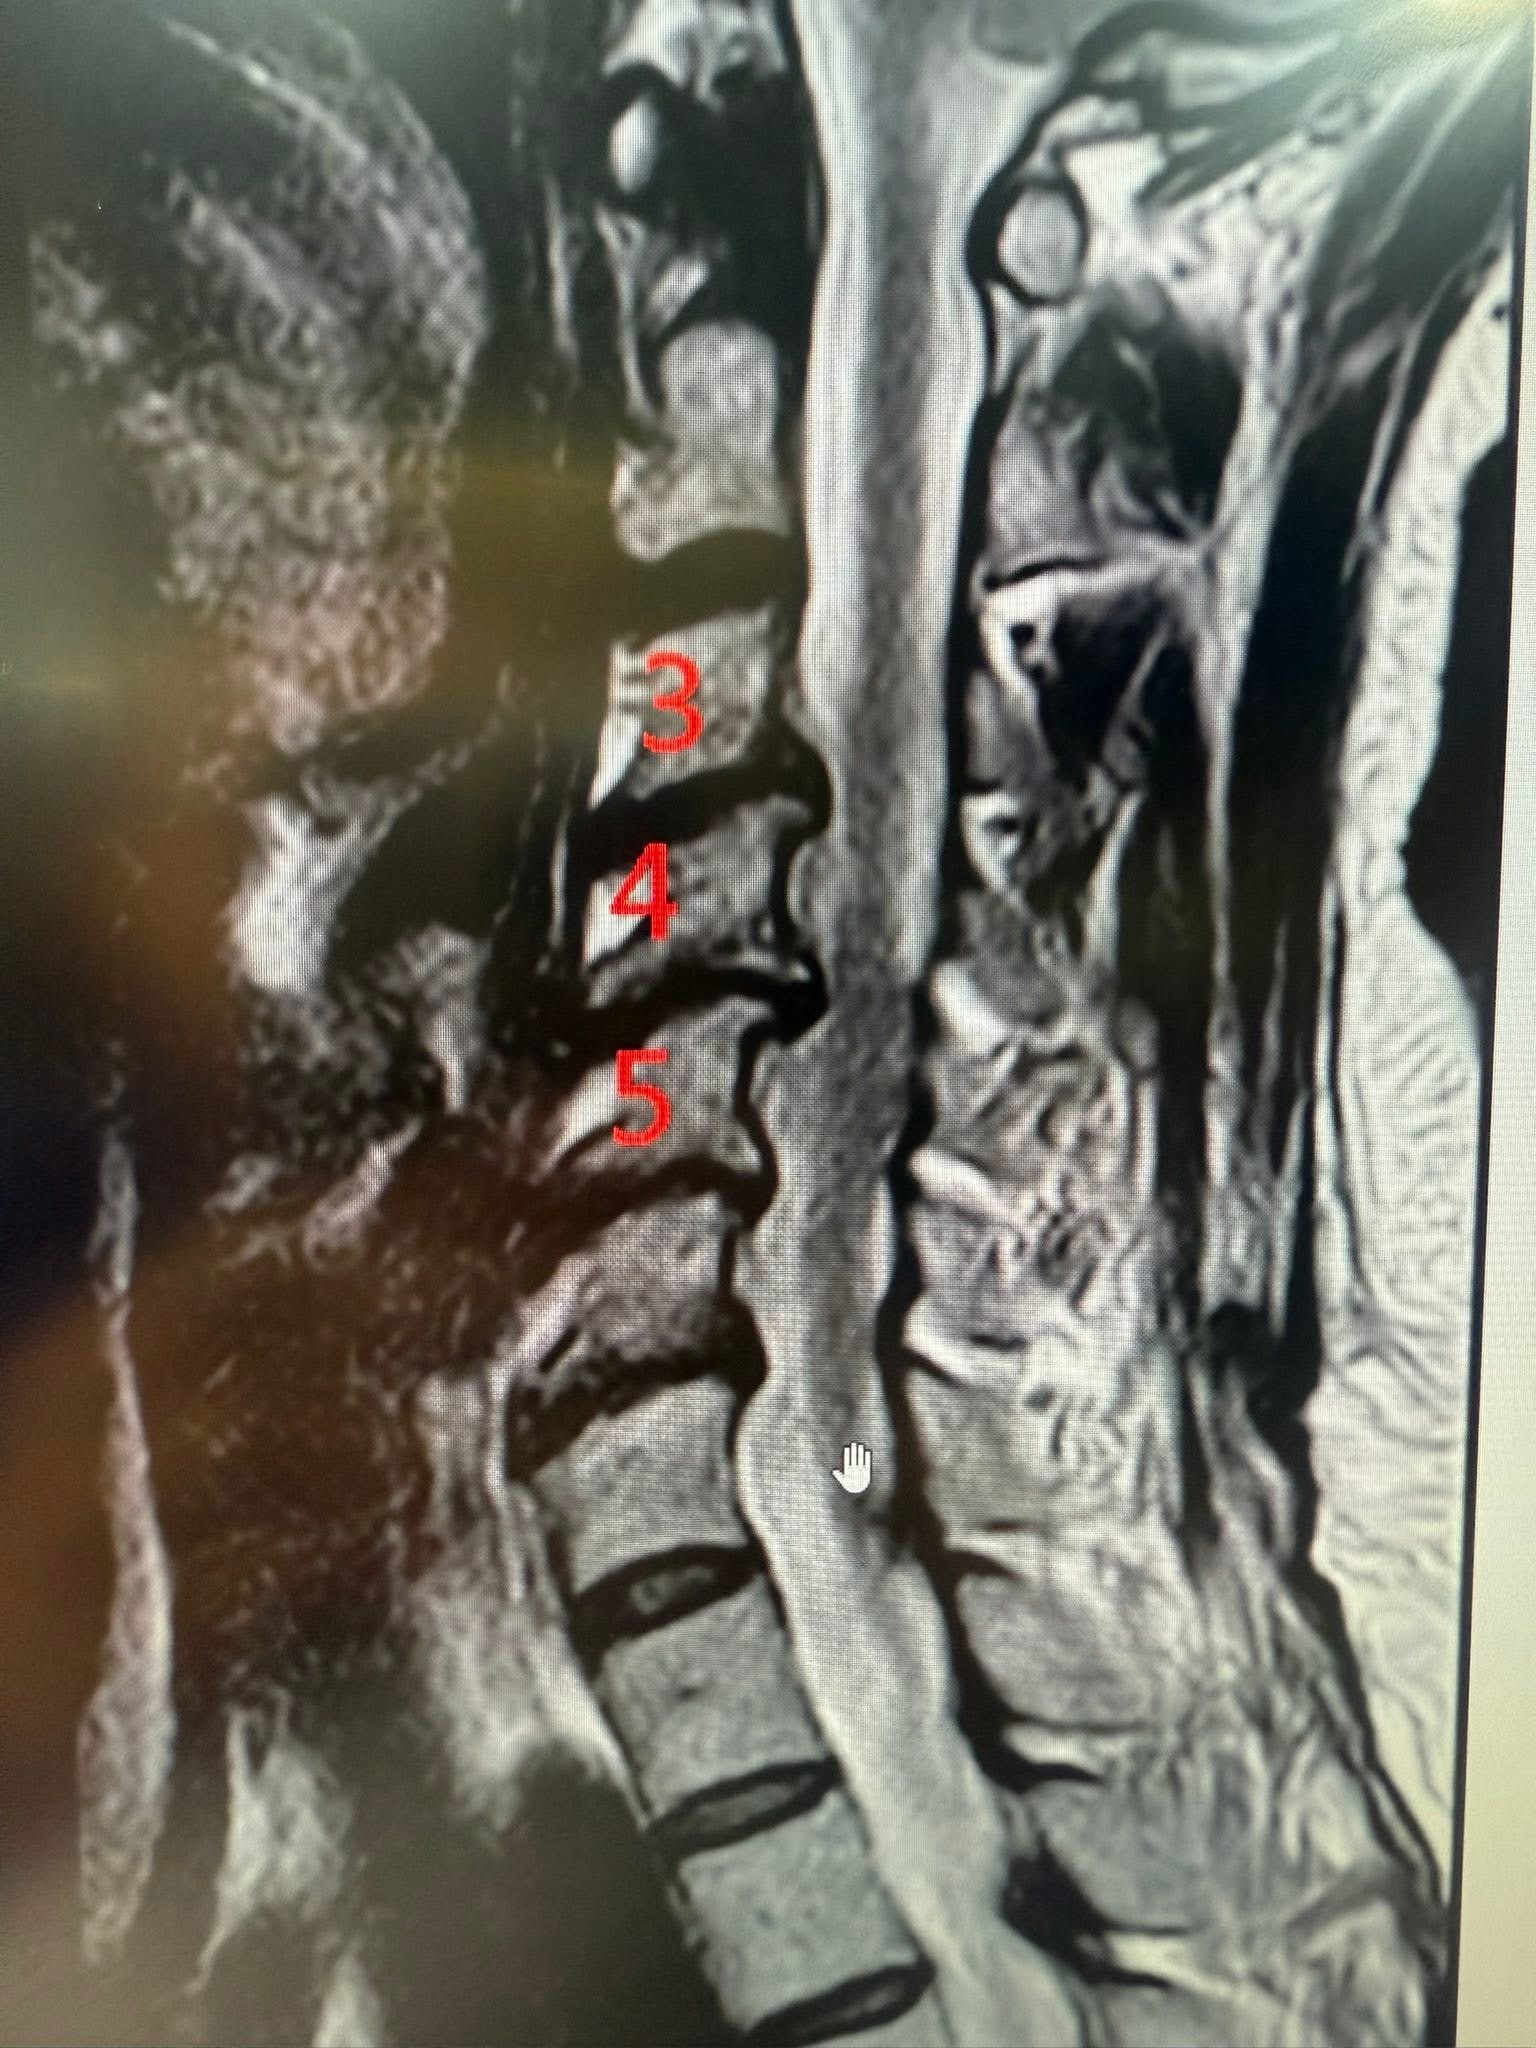

頸椎X光與MRI,真相很明確:

• X光顯示頸椎生理弧度變直,C5–C6不穩,前彎活動受限

• MRI則清楚看見C4/5、C5/6、C6/C三節都椎間盤突出,C5/6明顯壓迫脊髓與左側神經根